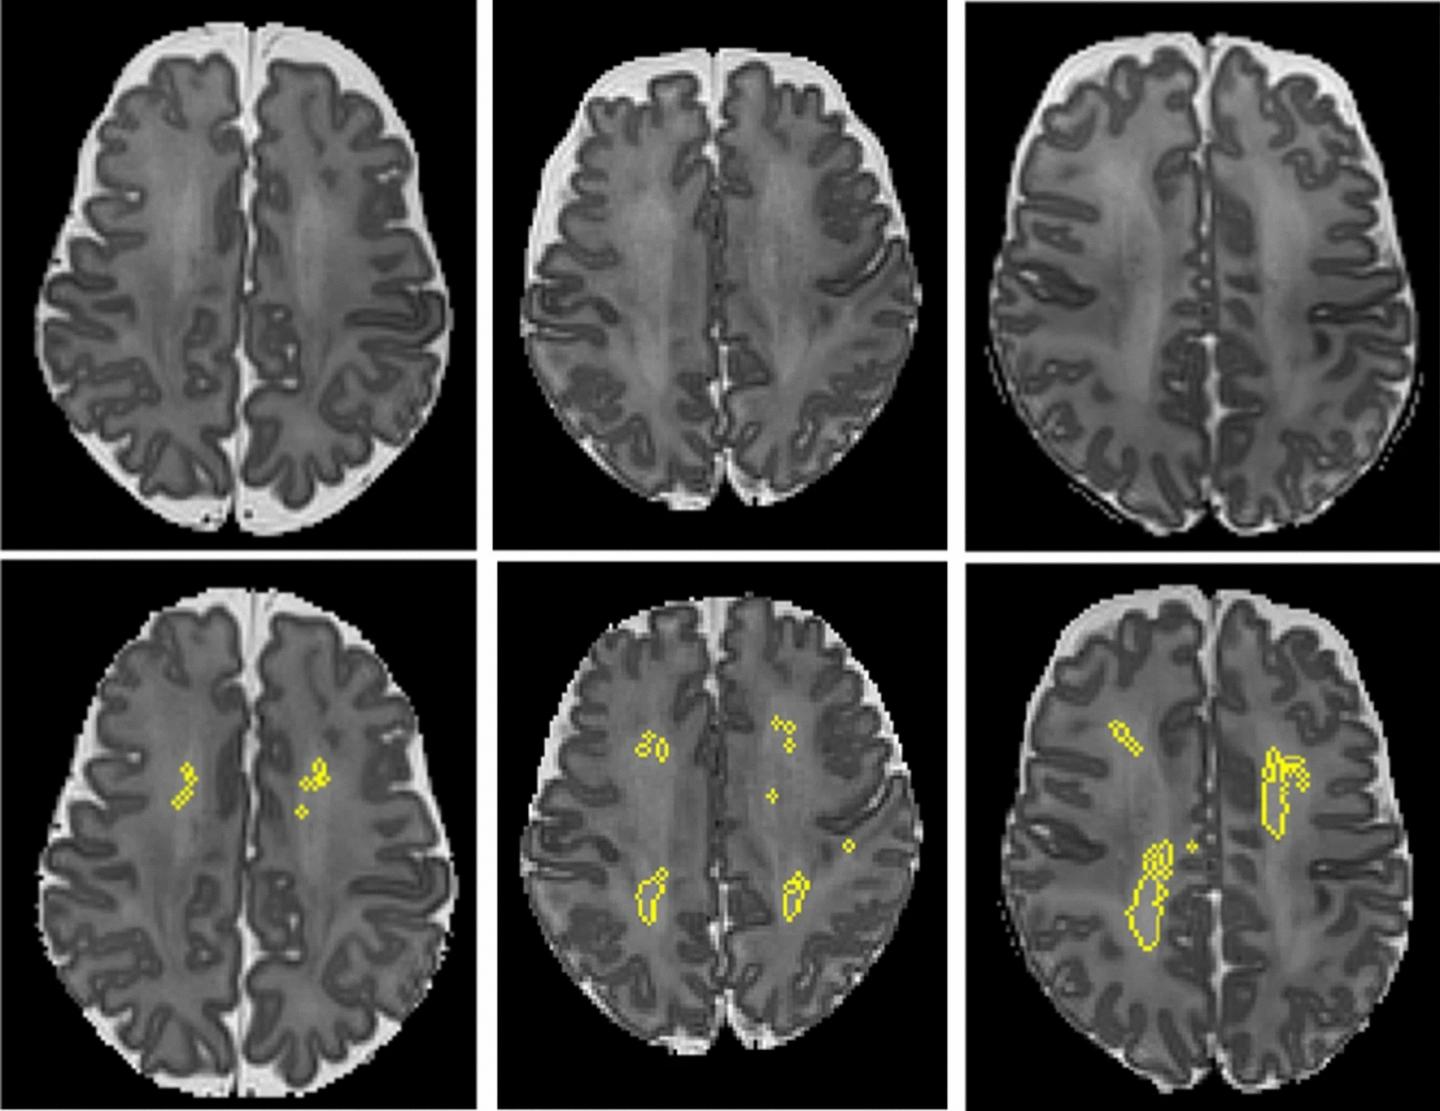

These MRI scans show diffuse white matter abnormality (DWMA). The top three panels display raw MRI images from very preterm infants born at 27 weeks (left), 26 weeks (center) and 31 weeks (right) gestation. Higher signal intensity can be seen in the central white matter, particularly for the 31-week gestation infant. The bottom panels display the corresponding slices with objectively segmented DWMA in yellow. The 27-week infant (left) was diagnosed with mild DWMA, the 26-week infant (center) was diagnosed with moderate DWMA, and the 31-week infant had severe DWMA. Image courtesy of Cincinnati Children's and Nature Scientific Reports

"While most researchers and doctors have concluded that DWMA is not pathologic, our novel studies are concluding otherwise," Parikh says. "Most studies have diagnosed DWMA qualitatively based on visual readings from radiologists (yes/no, mild/moderate/severe). These subjective diagnoses have been unreliable and therefore have not been significantly associated with neurodevelopmental disorders."

However, quantifying the volume of DWMA, does allow for risk stratification, Parikh says. The method also allows for earlier diagnosis. Currently, affected children are not diagnosed with these disorders until 2 to 5 years of age.